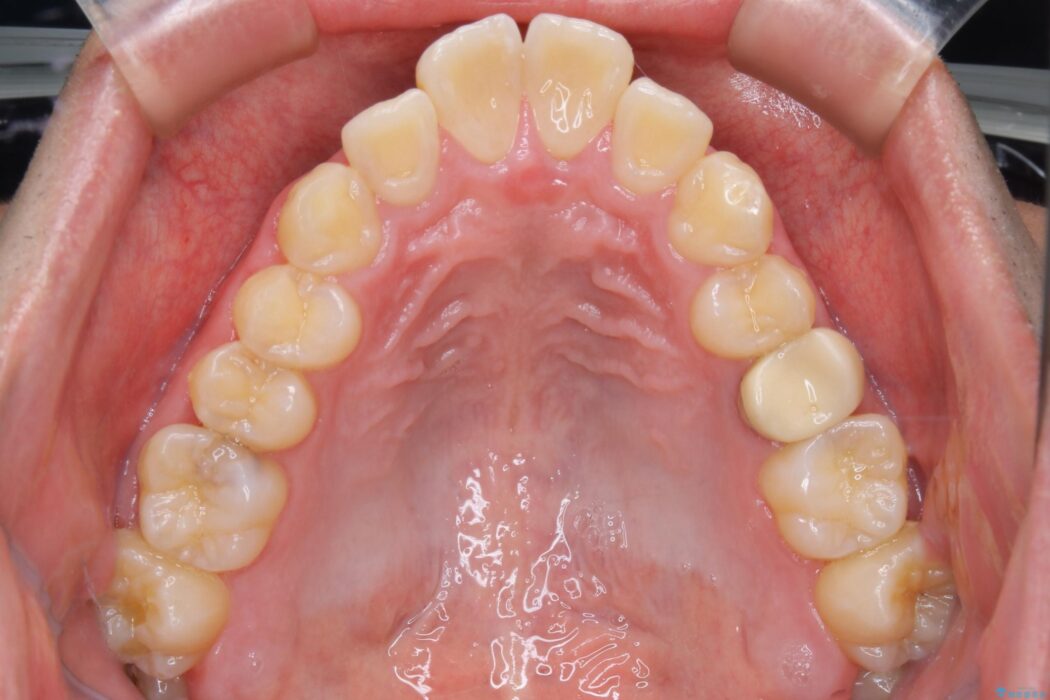

上の歯の出っ歯と下の歯のガタつきが気になるとご来院された患者様です。

出っ歯とガタつきの改善には抜歯が必要と診断し、上下左右第一小臼歯を抜歯することとしました。

抜歯でスペースができるため、歯の移動量が多いことから表側ワイヤー矯正装置で治療を行いました。

ワイヤー矯正、マウスピース矯正、それぞれの特性、得意な治療がありますので、患者様の状態に合わせた治療器具の選択が大事となります。